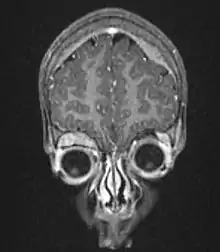

On microscopy, the tumor cells are typically described as small, round and blue, and rosette patterns (Homer Wright pseudorosettes) may be seen. Homer Wright pseudorosettes are tumor cells around the neuropil, not to be confused with a true rosettes, which are tumor cells around an empty lumen.[26] They are also distinct from the pseudorosettes of an ependymoma which consist of tumor cells with glial fibrillary acidic protein (GFAP)–positive processes tapering off toward a blood vessel (thus a combination of the two).[27] A variety of immunohistochemical stains are used by pathologists to distinguish neuroblastomas from histological mimics, such as rhabdomyosarcoma, Ewing's sarcoma, lymphoma and Wilms' tumor.[28]